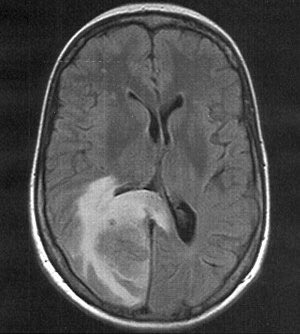

لأن النقص الحاد والسريع يَنجم عنه آثار خطيرة محتملة، كتورم الدماغ السريع، الذي يُمكن أن يُؤدي إلى الغيبوبة والوفاة.

مثال لحالة مريضة قلب في العناية المركزة مع ارتفاع شديد لمستوى الصوديوم

وصل إلى ( 180) ⛔️

وهنا كانت توصيتي الغذائية ⤵️